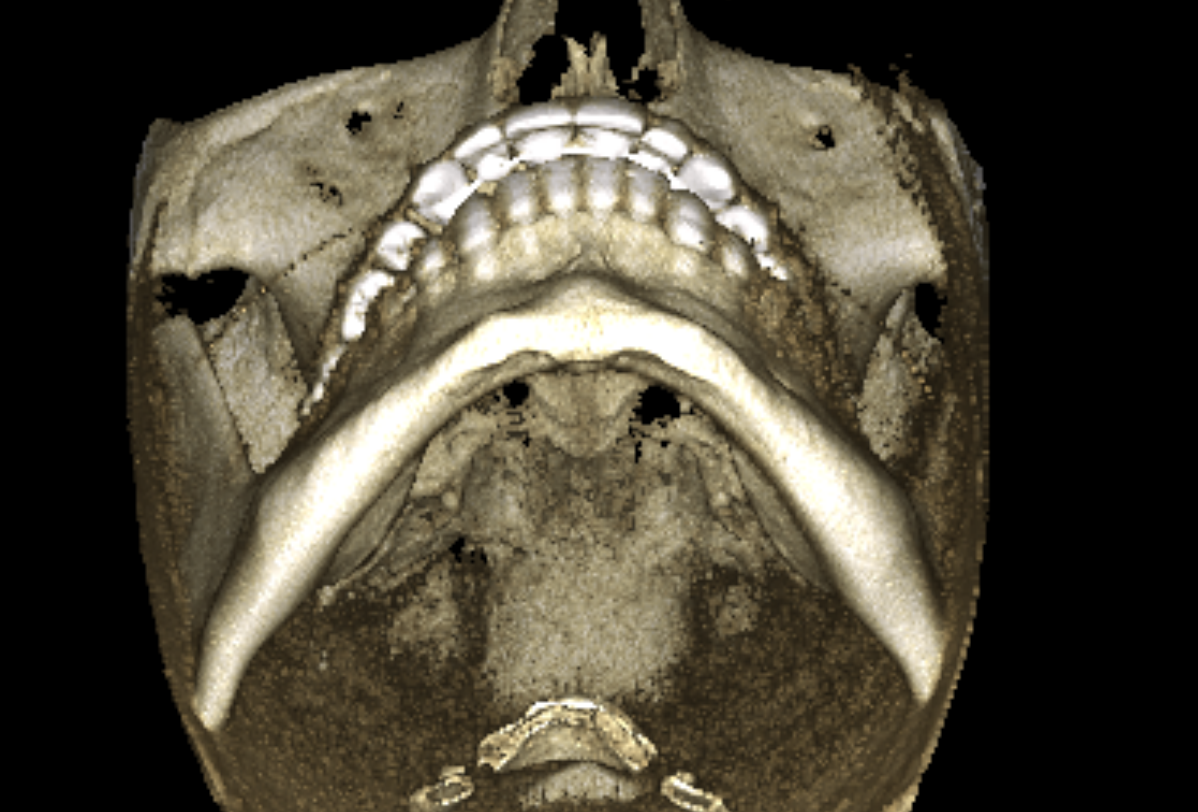

you can also see that my alveolar bone is short af vertically which causes lot of issues like lack of upper teeth show and small root on the teeth. in particularry my right incisor is hanging off by a thread:feelswah:

Dude first, you are right I just saw how fucked up that root was(still is), also seems like you have a permanent retainer on top, I wonder, you got this xray cbct or whatever the fuck this is called, because of a doctor's suggestion or on your own? like did a professional give you rough advice yet, also, you are right to be worried I mean I have seen jawhacks' "over-expanded" expander like 82+turns, and saw how fcked up the roots were, but it can be saved you are not fucked over yet, but I fear for you brother, and that's a rare thing lol, do whatever you can to get it right and fckin rot in orthodontic knowlage if you have to if that means you can debate your doctor or confirm for yourself that what he says is valid and not unnecessary

you cant see the roots there properly, here let me show you:

wtf this looks even worse, if I hadn't seen the poorly edited correction you made in the image I'd assume this is edite, how the fck do you get this result? I mean more power to you, prob getting a full implant at early 30s xd and the funny thing is that the implant most likely will be better